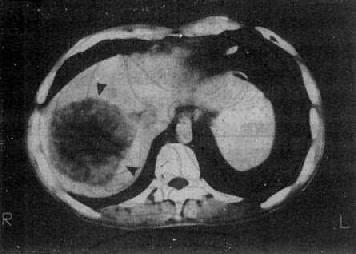

1.原发性肝癌 CT平扫绝大多数是低密度病灶,少数可以是低密度、等密度与高密度混合的病灶。肿瘤可以是单个或多个结节,也可呈巨块状。较大肿瘤因出血、坏死和囊变而致密度不均匀,中心部常出现更低密度区,其边缘部呈结节状。肿瘤边界多不清,少数边界清楚并有包膜。增强扫描肝癌区略有增强或不增强,而正常肝增强,因而使肿瘤境界更为清楚。癌变区可出现密度稍高的结节或隔,但其增强程度多不如正常肝。动态扫描时,即快速静脉注射造影剂并于开始注射后15~25秒内即行扫描,由于肝癌由肝动脉供血且供血丰富而迅速,而造影剂尚未到达肝内门静脉形成实质期,故肝癌结节可成为高密度,甚或显出高密度的异常肿瘤血管。但肝癌增强的时间较短暂,2~3分钟内即恢复为原来的低密度状态(图4-3-5)

图4-3-5 原发性肝癌

CT增强扫描,肝右叶有一较大圆形低密度肿块(↓),其边缘

部可见多个较密度的强化结节,其强化程度不如正常肝,中

心部仍为未强化的低密度区